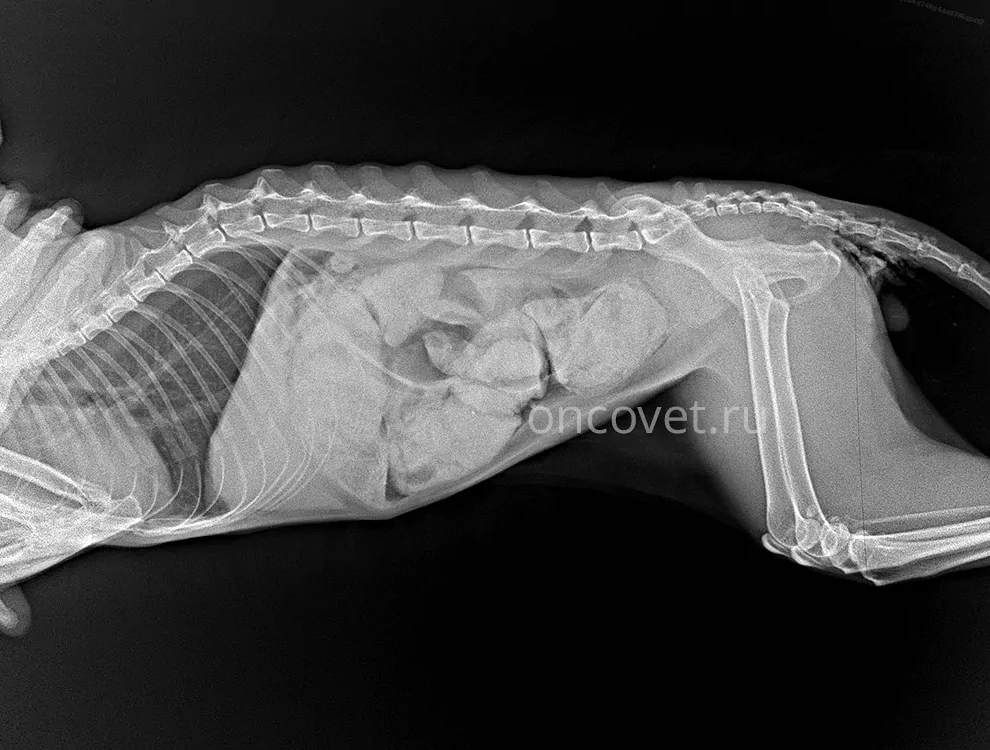

Список исследований, рекомендуемых ветеринаром, когда у кошки белый кал:

- общий анализ крови;

- кровь на биохимию;

- анализ каловых масс и мочи;

- узи внутренних органов;

- рентген;

- биопсия.